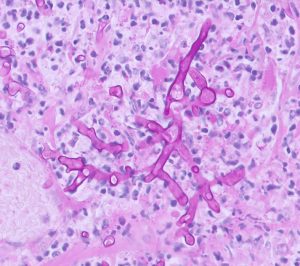

Figure 2 : Fungal hyphae found in the wall of the abomasum of a calf with abomasal ulceration (PAS stain)